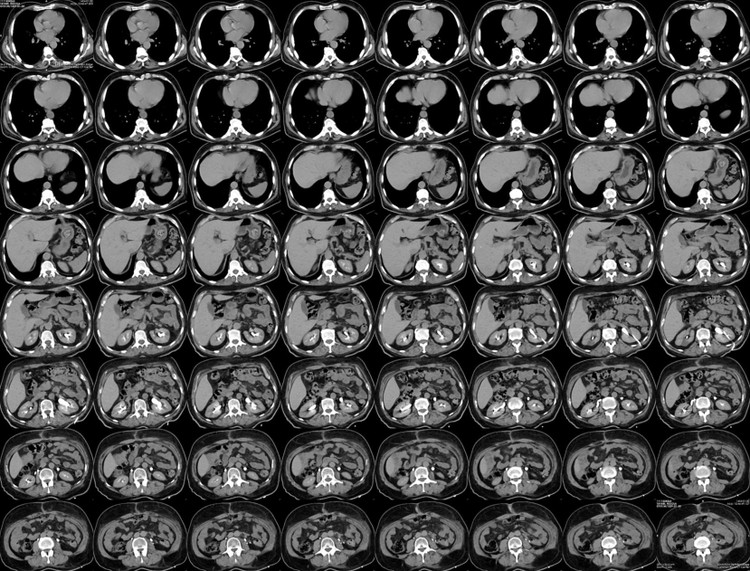

بی شک بلو فیلم های رادیولوژی با شاخص 1760 dpi به بالا جایگزین اقتصادی مناسب فیلم های رادیولوژی خواهند بود .

بدون شک شما میتوانید بدون پرداخت هزینه های سنگین و با پرداخت هزینه ای حدود نصف سایر فیلم های پزشکی مرکز تصویربرداری خود ( بخش های سی تی اسکن و ام ار ای ) را به خروجی کلیشه های تصویر برداری مجهز کنید .

با یک تماس و ارسال لینک از مرکز خودتان میتوانید بصورت رایگان از تصاویر مرکز خودتان نمونه دریافت نمایید .